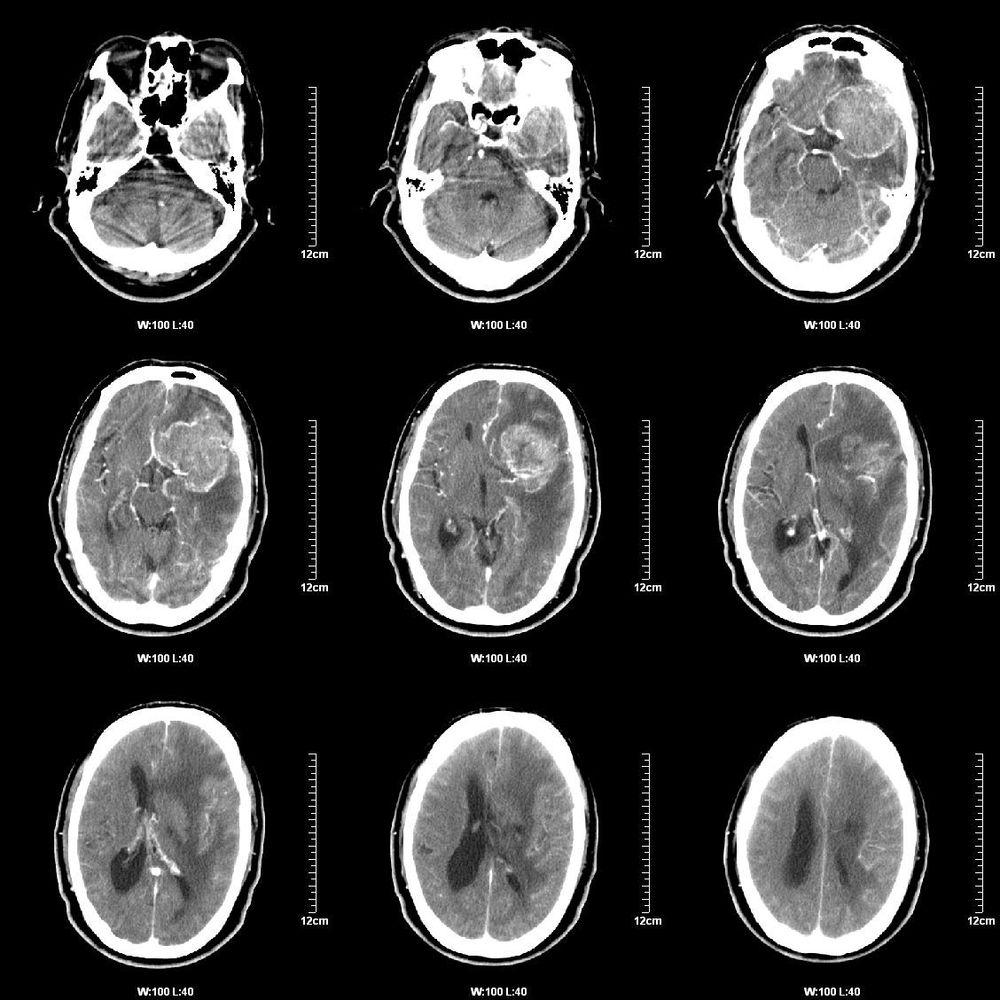

男,60岁。反应迟钝,胡言乱语20天余。

病灶不规则,密度不均,明显强化,周围水中,中线右偏,脑室受压。

考虑iii-iv级胶质细胞瘤。

病理没有出来,谈谈我们的看法,我们考虑较之母细胞瘤,理由是:

1、患者年龄较大,65岁;

2、病灶主体位于左侧大脑额叶白质内,并侵及邻近脑叶;

3、平扫呈等/低混杂密度灶,病灶内见灶状坏死,但病变区未见明显钙化灶。边缘不整,轮廓不清楚,周围脑组织水肿明显;

4、病灶强化明显,呈不均匀强化,枣状坏死部分无强化;

肿瘤位于左额颞顶叶,边界尚清,但不规则,增强后强化不均匀,瘤周水肿较甚,左侧脑室受压变形,中线结构向右移位首先考虑胶质瘤,不排除单发转移瘤

平扫显示左侧额、颞叶可见一类圆形混杂密度肿块,病灶以等密度为主,中央可见小斑片状低密度去,周围可见大片状的水肿,中线偏向右侧,侧脑室前角明显受压,增强扫描可见病灶呈现明显不均匀强化,中央坏死区未见强化,结合临床,考虑为胶质瘤(iii-iv级)